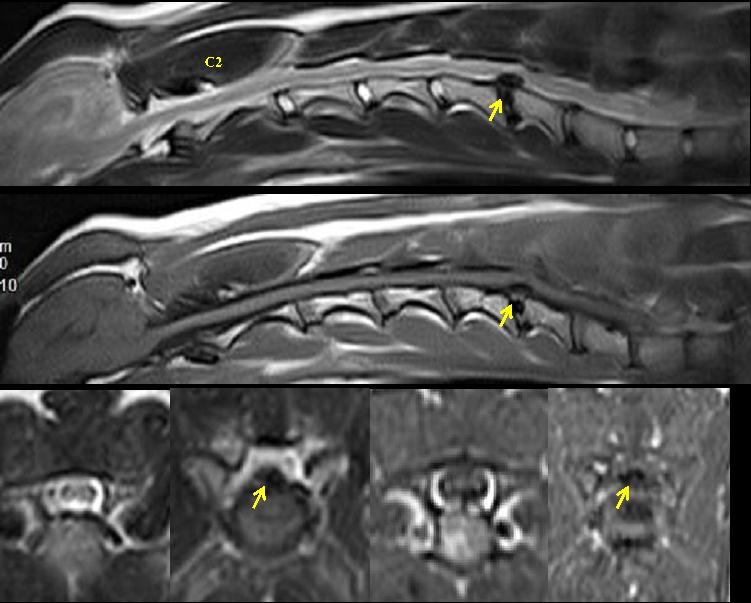

神经学病变定位:MRI检查,可见 C5-6 椎间盘矿化、脱出,椎管内占位明显,约为 50%,局部脊髓受压变形(见图1)。C1-C5脊髓神经损伤,瘫痪程度3/5。

图1 Vega的颈部MRI影像

痹证的主要症状是疼痛,疼痛为气血瘀滞,经络不通的表现。颈部痹证可分为气滞和血瘀两种。气滞的患病动物在触诊时颈部有轻微的疼痛,或者只在后肢有轻微的共济失调。在X线片上也无明显变化。在血瘀的患病动物,有明显的四肢共济失调,X线影像可能有椎间盘间隙狭窄、半关节面硬化等。诊断需要依靠脊柱影像学检查,MRI优于脊髓造影或者CT。由于Vega具有明显的四肢共济失调,站立和行动困难,而且MRI结果显示C5-C6有明显的椎间盘脱出;因此,诊断该犬为血瘀,其治疗方案以活血化瘀止痛为主。